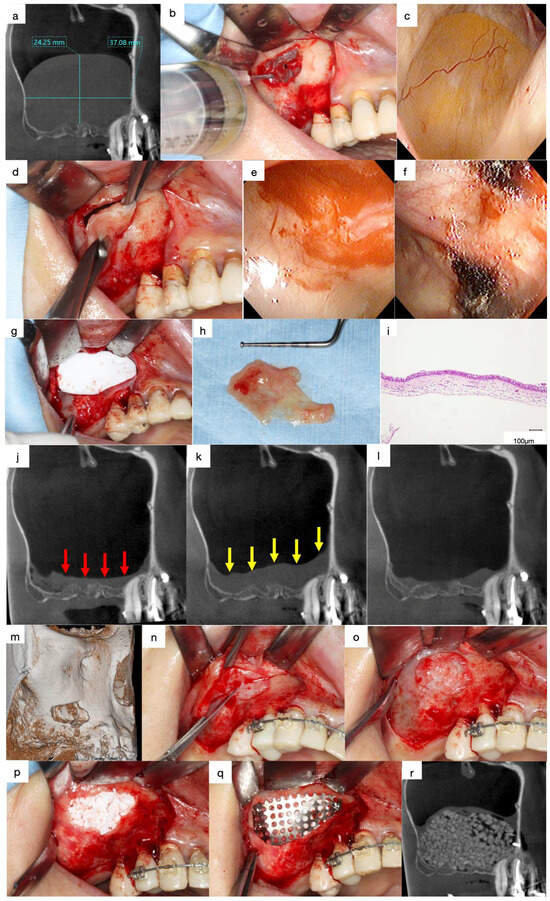

Preliminary suction of the contents was performed with a fine 18-gauge needle in cases with large APs (>15 mm) to reduce the volume to facilitate the clamping of the AP (Figure 5a,b). The surface of the AP was clamped with forceps and herniated through the bony window with gentle outwards traction without preserving the integrity of the periosteum underneath the AP (Figure 5c,d). The base of the AP, which appears as a sessile dome-shaped, well-defined, faintly radiopaque lesion, is usually present on the floor of the sinus cavity. In contrast, the AP appears as a round when the base of the AP is present at the lateral wall of the maxillary sinus (Figure 3a,b). The position of the base must be evaluated preoperatively as the AP, including the base, should be enucleated together.

Figure 5.

(a) Mesiodistal section of the CT images acquired at the first visit. A large, well-defined, and faint radiopaque lesion can be observed in the maxillary sinus. (b) Preliminary suction of the lesion contents was performed using a fine 18-gauge needle. (c) Endoscopic view of the antral pseudocyst (AP) after suction of the contents. The AP has reduced in size compared to that observed on the CT images during the preliminary section. (d) The surface of the AP was clamped with forceps and herniated through the bony window with gentle outwards traction. (e) Endoscopic view of the enucleated area. A contentious haemorrhage was observed at the base of the AP. (f) Oxidised regenerated cellulose was applied to stop bleeding. (g) The bony window is covered with a resorbable collagen membrane to reduce blood flow into the sinus cavity. (h) The AP was enucleated as a lump with a base. (i) Histological specimen of the enucleated AP (haematoxylin and eosin staining). The outer surface of the lesion was lined with ciliated columnar epithelium and the inner surface was lined with fibrous connective tissue without epithelium. (j) Mesiodistal section of the CT image obtained after enucleation. A flat, faintly radiopaque area can be observed, demonstrating an accumulation of physiological saline or blood at the bottom of the maxillary sinus (red arrows). (k) Swelling of the sinus membrane increased one-week following enucleation (yellow arrows). (l) Swelling of the sinus membrane decreased three months after enucleation. (m) Volume-rendering image obtained three months after enucleation. The bone defect persists in the bony window. (n) Dissection of the scar tissue between the sinus membrane and oral mucosa was necessary at the bone defect area to avoid perforation of the sinus cavity. (o) Scar tissue was observed in the bone defect area without perforation after the elevation of the mucoperiosteal flap. (p) β-TCP granules fill the space between the elevated periosteum and the exposed bone surface of the maxillary sinus. (q) The bony window was tightly covered with a titanium mesh plate and three titanium microscrews. (r) Mesiodistal section of the CT image obtained after sinus floor elevation. Sufficient radiopaque granules can be observed in the augmented area.

The use of an endoscope is not mandatory; however, it aids in confirming the enucleation of APs and haemostasis through the small bony window. Haemostasis was performed using oxidised regenerated cellulose in cases with continuous haemorrhage (Figure 5e,f). The bony window was covered with a resorbable collagen membrane to reduce blood flow into the sinus cavity, and the mucoperiosteal flap was closed (Figure 5g).

4.4. Lateral Approach after Enucleation

Swelling of the sinus membrane is observed due to traumatic stimulation one week post-surgery (Figure 5j,k), which diminishes three months later (Figure 5l). The ciliated columnar epithelium cells at the base of the AP are removed during the enucleation, and the periosteum underneath the AP is exposed. Hence, the decrease in the swelling of the sinus membrane indicates the regeneration of the columnar epithelial cells and restoration of the ciliary motility. Thus, sinus floor elevation can be performed four months following enucleation of APs.

Bone defects in the bony window persist for four months following the enucleation of APs (Figure 5m). Therefore, dissection of the scar tissues between the sinus membrane and oral mucosa must be performed in the area with the bone defect during the elevation of the mucoperiosteal flap for sinus floor elevation using the lateral approach (Figure 5n,o). The periosteum underneath the sinus membrane is elevated after enlarging the bony window, and the β-TCP granules are filled in the space between the elevated periosteum and the exposed bone surface of the maxillary sinus (Figure 5p). The bony window is covered tightly with a titanium mesh plate and three titanium micro screws to avoid the migration of the β-TCP granules due to the postoperative sealing of the sinus membrane (Figure 5q,r) [5].